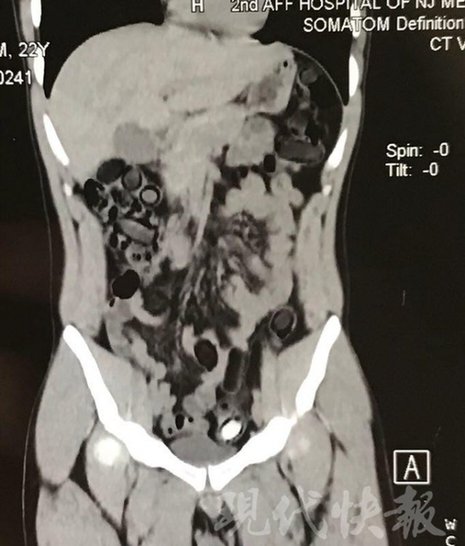

小伙體內(nèi)藏毒300余克 CT掃描圖密密麻麻全是蠶蛹

由于毒品在體內(nèi)一旦泄露有可能致命,警方第一時間將阿永帶到醫(yī)院進行檢查。CT 掃描的結(jié)果顯示,阿永體內(nèi)布滿了密密麻麻的白色圓柱狀固體,就像一粒粒的蠶蛹。在南京市公安局鼓樓分局二板橋派出所,阿永分四次排出了毒品,毛重369.99克。經(jīng)訊問,阿永交代了自己全部的犯罪事實。目前,阿永已被刑事拘留。